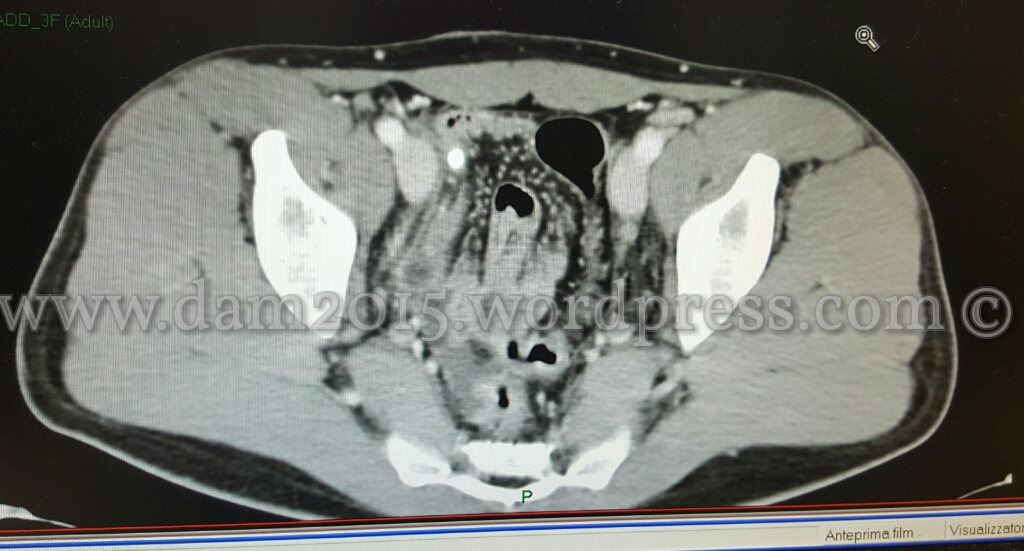

Alla TC con mezzo di contrasto si evidenziava distensione fluida dell’appendice cecale a localizzazione pelvica, nel cui lume si apprezza appendicolita.